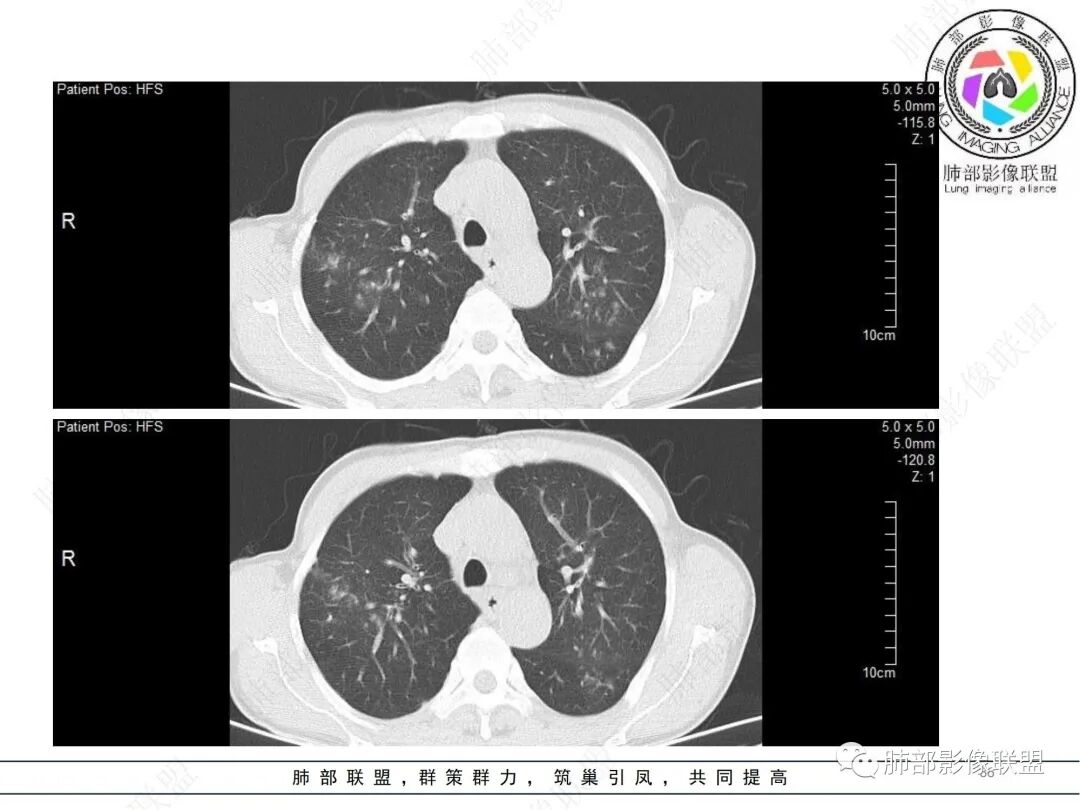

58岁男性,咳嗽胸闷3天,咳较多褐粘液痰,无发热。有2型糖尿病病史。白细胞与中性粒细胞升高。CRP升高。鳞状上皮细胞癌抗原轻度升高。结核T细胞免疫斑点实性阳性。肺炎支原体、衣原体IgG轻度升高。支气管镜显示支气管炎性改变、右肺下叶背段管腔狭窄。2.影像特点:

2022.6.24CT显示两肺弥漫性段、亚段支气管壁增厚(两肺各叶都累及),增厚的支气管壁外可见沿着支气管分布的渗出、实变影。另外远端肺内亦可见多发树芽影、结节影,其边界欠清晰。右肺下叶基底段局部胸膜下亦可见小斑片影,边界不清。2022.6.27CT显示两肺增厚的支气管壁外的渗出实变影明显增多、范围更广。远端肺内病灶亦增多、范围增大。部分位于胸膜下的病灶可见侧向融合趋势。3.病例分析: